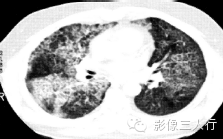

| 病毒性肺炎(图1) | 粟粒性肺结核(图2) | 细支气管肺泡癌(图3) | 肺尘埃沉着病(图4) | 肺泡蛋白沉着症(图5) | 血吸虫病(图6) | |

散在分布,6〜8mm或更小 | 分布均匀,直径1〜2mm | 分布不均,直径6〜7 mm | 分布不均,直径多为2〜5mm | 地图样、铺路石征 | 大小不等,直径多为1〜5mm |

较模糊 | 较清楚或较模糊 | 较清楚 | 较清楚 | 较清楚 | 较模糊 |

病灶密度相同,大小不等 | 病灶密度相同或不同 | 病灶密度相同,呈含气支气管征及蜂窝征 | 病灶密度不均,有钙化 | 磨玻璃密度,地图样分布和铺路石征 | 病灶密度不均,典型者可见晕征 |

(B)平扫二